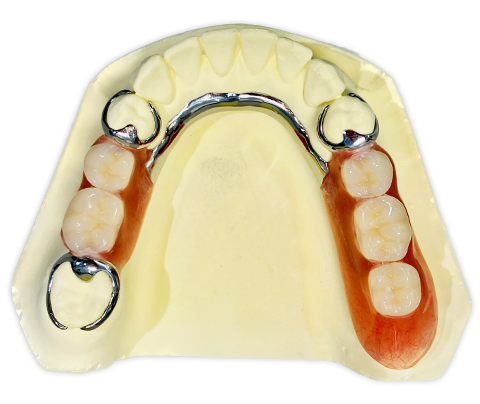

【始めにこちらをお読みください】・本商品は裁断済みです。・スキャン目的のため、1ページずつバラバラの状態になっています。・裁断済みのためやや傷や汚れありのコンディションにしていますが、中のページにつきましては、書き込みや大きな汚れはなく、比較的良好な状態です。・裁断済みであることをご理解のうえ、ご購入をお願いいたします。・裁断済みを理由とした返品はご容赦ください。・まとめ買いご希望の方はお気軽にご申請下さい。長期症例に基づいたパーシャルデンチャーの包括的医療における重要性を解説した一冊。- 出版社: クインテッセンス出版定価(本体12,000円+税)ご覧いただきありがとうございます。